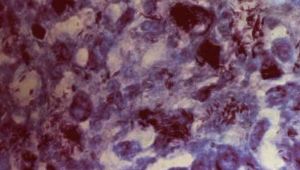

麻風桿菌麻風桿菌,病原菌是麻風桿菌,在光學顯微鏡下完整的桿菌為直棒狀或稍有彎曲,長約2~6微米,長約0.2~0.6微米,無鞭毛、芽孢或莢膜。非完整者可見短棒狀、雙球狀、念珠狀、顆粒狀等形狀。數量較多時有聚簇的特點,可形成球團狀或束刷狀。

麻風桿菌抗酸染色為紅色,革蘭氏染色為陽性。

常在病人潰破皮膚滲出液的細胞中發現,呈束狀排列,以麻風桿菌感染小鼠足墊或接種至犰狳可引起動物的進行性麻風感染,為研究麻風的一種動物模型。麻風桿菌口侵害人,可通過皮膚接觸,或由飛沫傳播,細菌由病人鼻分泌物及其他分泌物、精液或陰道分泌液中排出而感染他人。疾病潛伏期長,發病慢,病程長,遷延不愈。根據臨床表現、免疫病理變化、細菌檢查結果等可將麻風病分為瘤型麻風和結核樣型麻風。